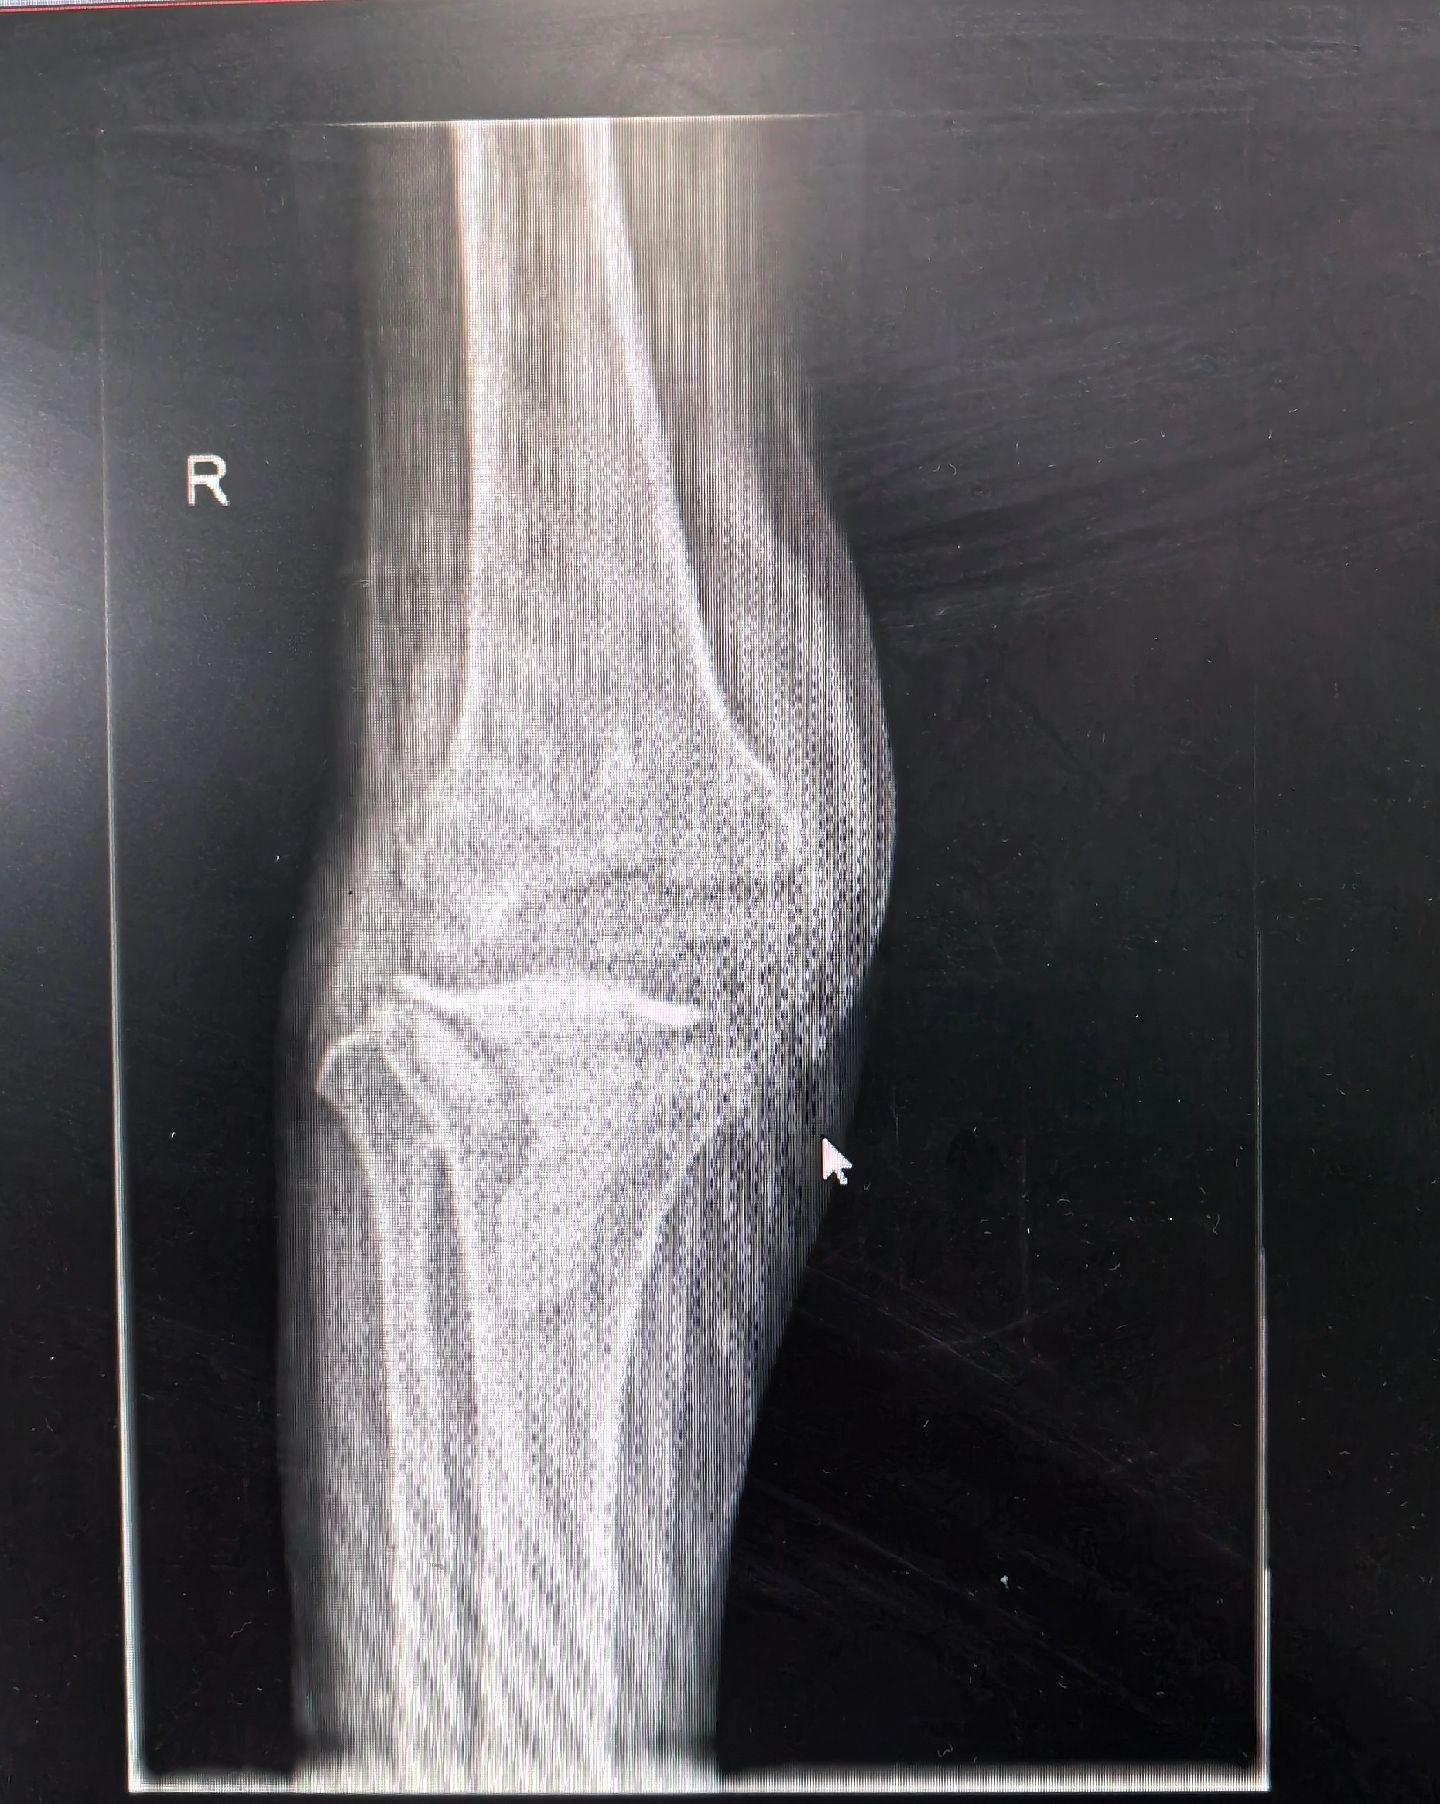

膝关节翻修。PJI,二期翻修。关节置换,谨防感染。